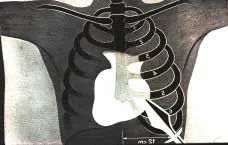

| Neste sangue e nesta água que saíram do flanco, os médicos concluíram que o pericárdio, (saco membranoso que envolve o coração), deve ter sido alcançado pela lança, ou que se pôde ocasionar perfuração do ventrículo direito ou talvez havia um hemopericárdio postraumático, ou representava fluido de pleura e pericárdio, de onde teria procedido a efusão de sangue. | ![]() |